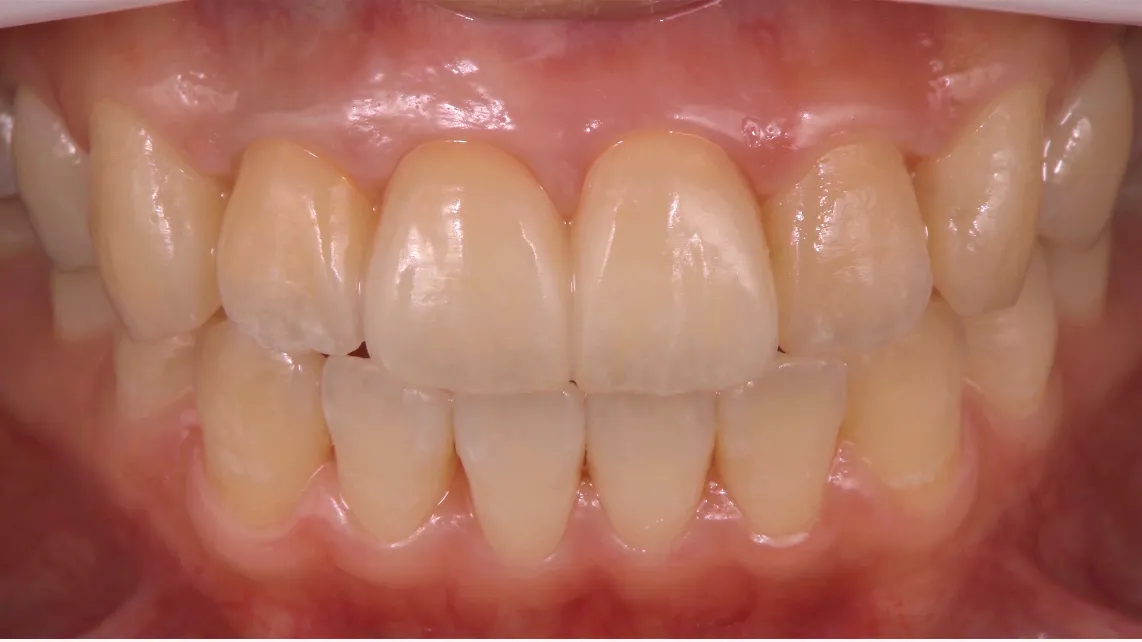

歯並びや歯の色と同様に、歯茎が黒いのも多くの方のコンプレックスになっています。笑った時に、歯茎が黒いと相手に与える印象は決して良くはありません。 歯茎が黒い原因は5つあります。それぞれの原因と治療法をご紹介致します。

②歯周病

日本国民の80%が歯周病と言われています。歯周病で歯茎が黒くなってる方も、多いのではないでしょうか。

歯周病にかかると、歯茎は炎症を起こし赤黒く変色していきます。また歯周病の原因である黒い歯石が歯茎の中に溜まると、より一層歯茎が黒くなる原因にもなります。